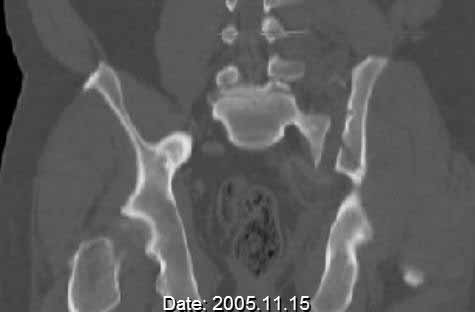

Patient was prone for procedure, as I thought too difficult to fix the wing in lateral position. Of course the repair of wing was easy, but reduction of SI very demanding. The Floro images document the residual lack of reduction. That was the closest I could get it using 6mm joystick in wing, and clamp on sacrum and clamp through notch.  The fixation was (initially) rigid. Anterior ex fix with supra-acetabular pins was placed due to condition of soft tissues, massive "beer-belly" overhanging the crest.

5. Your caudal iliosacral screw is/was in his spinal canal...it's low and posterior and the lateral fluoro image confirms this...a postop CT will show it (or it's trail at this point)...canal screws do not hold.